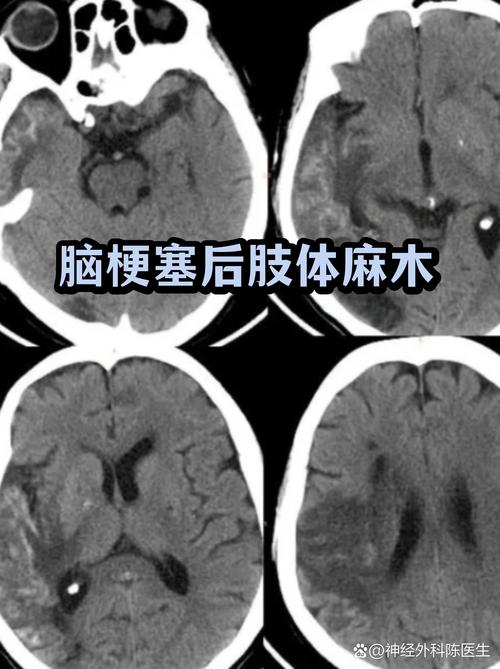

- 表现:一侧肢体麻木、针刺感、感觉迟钝或过敏。

- 恢复规律:感觉恢复通常比运动功能恢复得慢,有时需要更长时间。